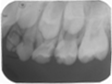

65MO深大龋洞,色棕黄,质软,叩痛(+),不松动,牙龈红肿,未见瘘管。 X线片示:冠部低密度影达髓腔,根分歧区大面积低密度影,近远中根内侧壁见吸收。25牙胚存,未拍全。 64MO深大龋洞,色棕黄,质软,叩痛(+),不松动,牙龈略红肿。 X线片示:根分歧区密度减低。 84OD深大龋洞,色棕黄,质软,叩痛(-),不松动, 85MO牙色充填体周围见龋坏,色黑,质软,叩痛(±),不松动,龈无异常。 X线片示:根周见低密度影,44,45牙胚存,未拍全。 54DOL深大龋洞,色黑,质软,叩痛(-),不松动, 55O窝沟色黑,卡探针,叩痛(-),不松动,龈无异常。 74OD,75MO半年前曾于外院行充填治疗,现检查见充填体边缘色黑,卡探针,充填体略有松动。